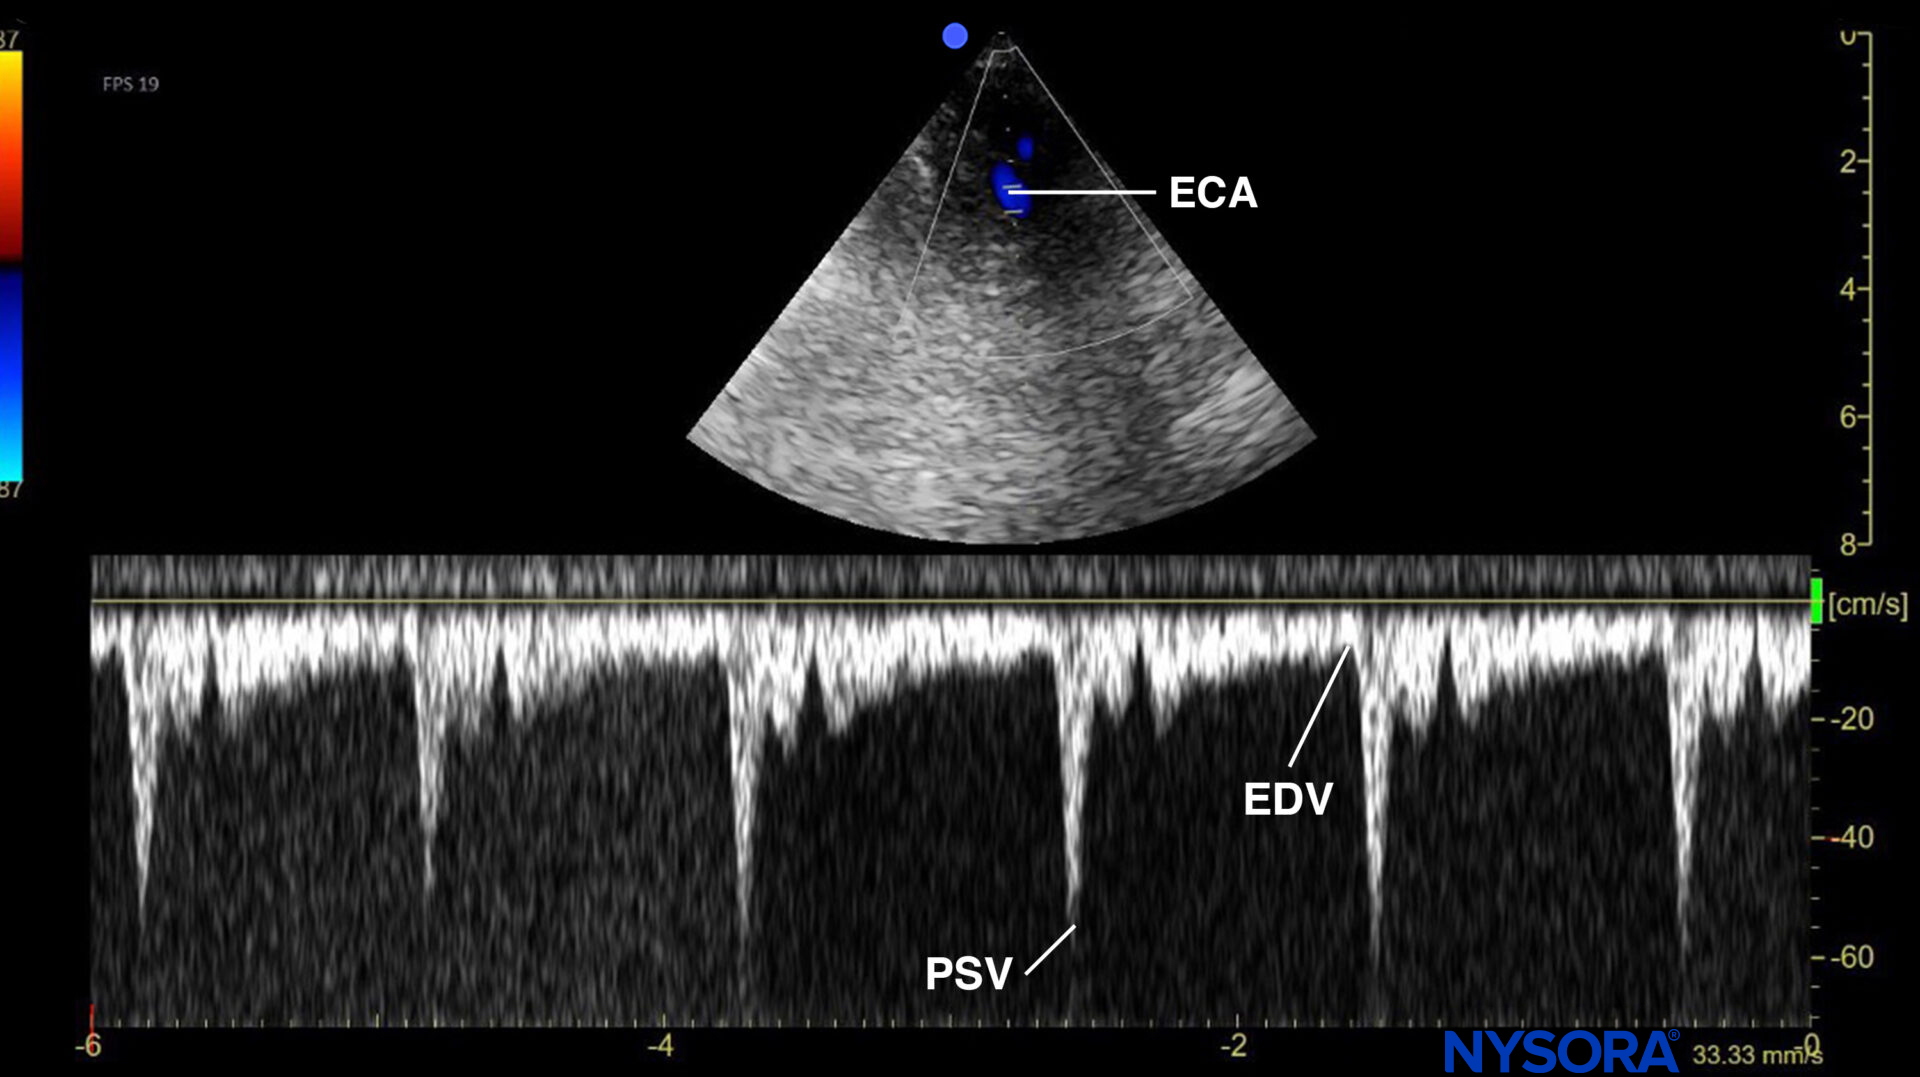

Pulsed wave Doppler of the flow in the external carotid artery (ECA) with the typical flow profile of a ‘high resistance’ circulation, with a steep decline after the systolic peak, and relatively low diastolic flow velocities. PSV, peak systolic velocity; EDV, end-diastolic velocity.